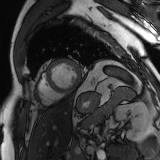

Refer to caption

Figure 2: Examples of tracking results using the proposed method (MPN-C). From left column to right: ED frame, ES frame, warped frame from ED, overlay of ES frame and the warped mask, and estimated motion field using HSV color coding. The color coding wheel legend indicates the motion directions.